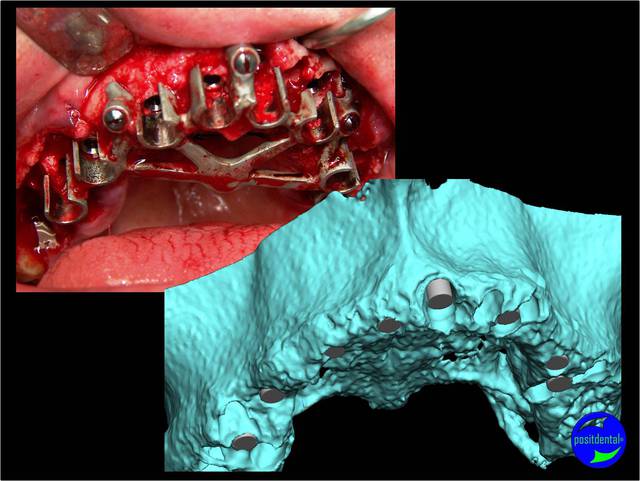

contrôle d'un des cas à 1 mois

24/05/2019 à 18h53

Je viens de revoir au cabinet un des 3 cas, car la céramique de la 25 était fracturée.

J'ai pris une photo (iphone) avec le bridge déposé avant de mettre temporairement le bridge coping de Posit. Pas la peine de commenter le bas je n'en suis pas responsable.